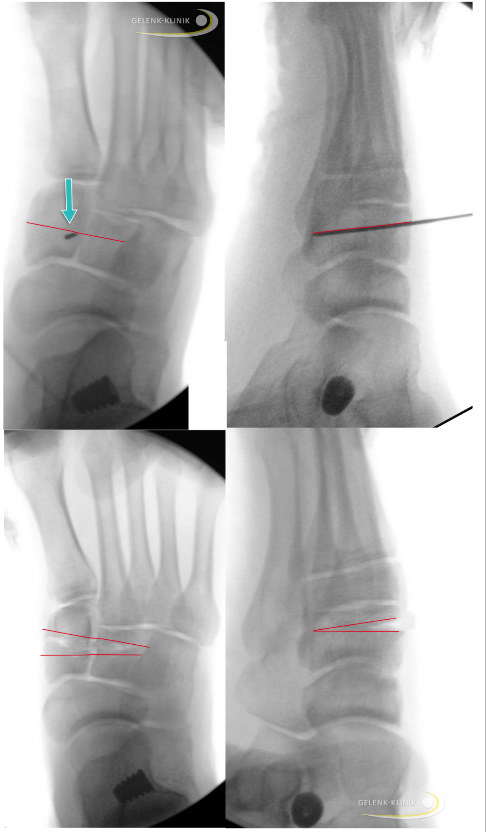

Intraoperative radiologische Kontrolle bei Cotton-Osteotomie: Nach Einbringen des Kirschner-Drahts und Überprüfung seiner Lage erfolgt dann die Durchtrennung (2/3 des Knochens) und anschließend die schrittweise Aufbiegung im Knochen. Im weiteren Verlauf wird der aufgespreizte Knochen mit einem Implantat gesichert. Die unteren beiden Bilder zeigen die Aufspreizung der beiden benachbarten Knochen Os cuniforme mediale und Os cuniforme intermedius. © Gelenk-Klinik

Die Cotton-Osteotomie wird meist in Vollnarkose und in Rückenlage des Patienten durchgeführt. Oft ist sie der letzte Teil einer komplexen Knick-Senkfußoperation. Nach entsprechender Behandlung der Weichteile mit Sehnenverlagerung und Lösung von Sehnen löst der Operateur das Periost und markiert das Operationsgebiet mit einem Draht.

Unter Bildwandler wird die geplante Osteotomie dargestellt, anschließend erfolgt die präzise Durchtrennung des medialen Keilbeins mit einer Säge. Dann bringt der Fußchirurg spezielle Drahtspreizer und Meißel in den Knochenspalt ein. Nach Aufspreizen des gesägten Spalts wird die Stellung des Vorfußes mehrfach überprüft und die passende Größe des Implantats bestimmt.